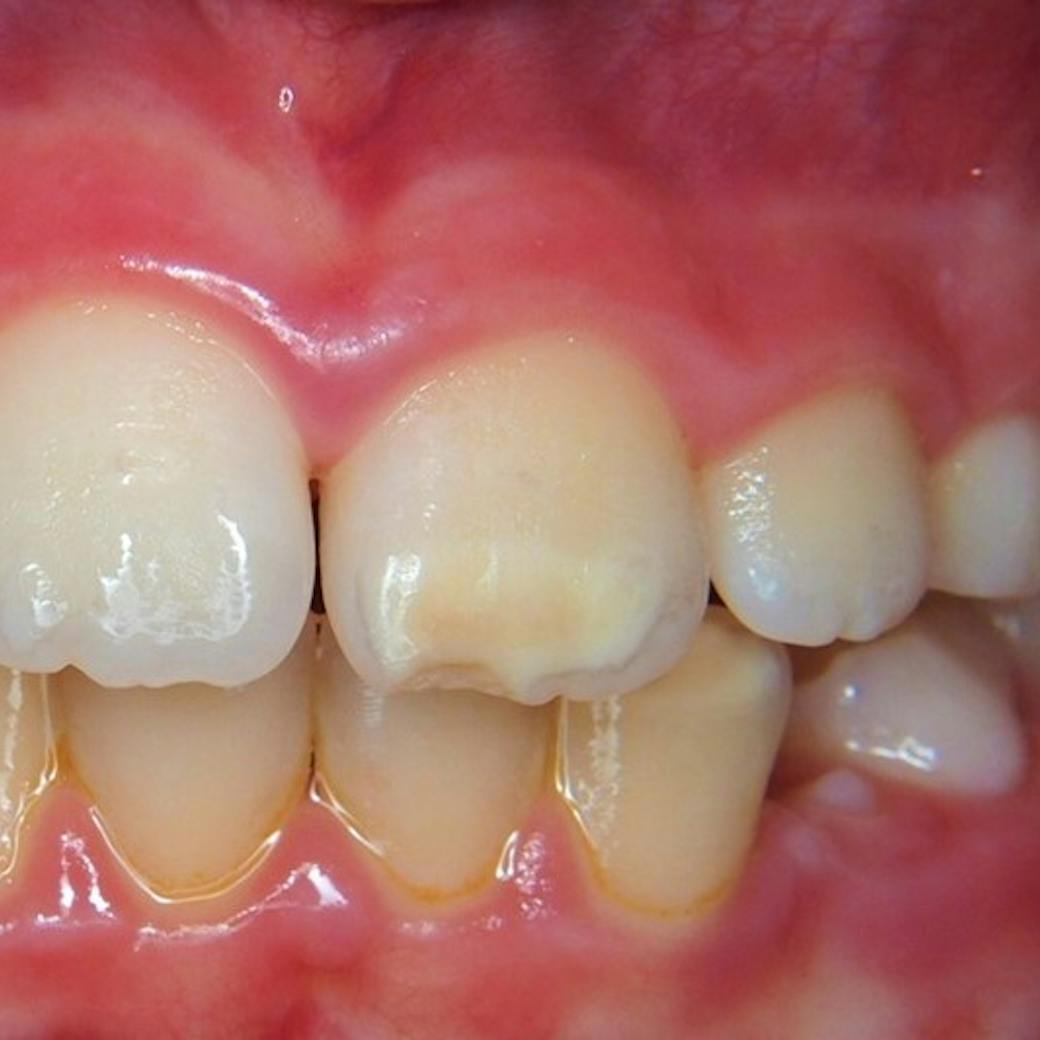

MIH som har fått en stigende prevalens blant barn og ungdom i de siste 10 år, er en diagnose på en ødelagt og svak emalje for 6 årsjeksler og fortenner.

MIH på en 6 års jeksel

Emaljen på disse tennene lages fra 8 uker i fosterstadiet frem til 4 årsalder. Emaljen som er ødelagt er gul og til dels hvit porøs, tannen iser raskt og er veldig ømfintlig på kald og varm mat/drikke samt på tannpuss. Diagnosen MIH ble først vitenskapelig beskrevet i 1987, og det var svært sjelden at den ble observert. Observasjon 30 år senere viser at opp til 15 % av skolebarn, også her i Norge, har den forstyrrelsen på tennene. En studie utført i Tyskland (DMS/5. V Deutsche Mundgesundheitsstudie) viser at hver tredje 12 åring har denne emalje forstyrrelsen. Dette kan jeg også bekrefte av våre observasjoner her på klinikken, økningen blant barn og ungdom har vært påfallende høy. MIH er nå oftere å se enn karies, uten riktig behandling og oppfølging av tennene er de også mye mer utsatt for å få karies.